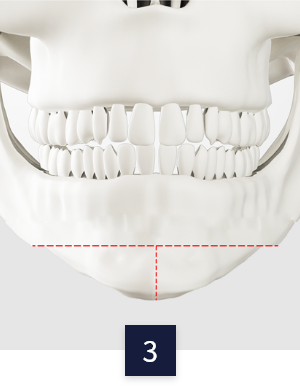

CASE 03

ㅡ절골

수술 방법

수술 전 턱

무턱 or 주걱턱 등 맞는

수술법을 찾아 수술 진행

턱 끝 전진술

턱 끝 뼈를 절골 후

앞으로 움직인 후 고정

턱 끝 후진술

뒤로 움직인 후 고정